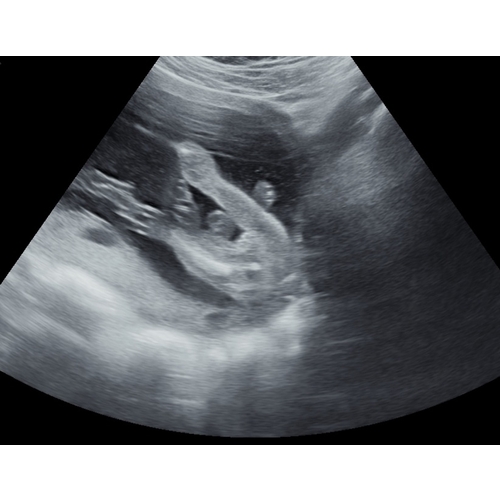

Vanaf zo'n 14w is het op zich wel redelijk goed te zien met een pottyshot. Alleen is het op deze foto niet goed te beoordelen omdat dit niet echt in een pottyshot houding is maar de baby in handstand 😉 Nu steekt er niks uit wat zou kunnen wijzen op meisje maar de pipi kan ook verborgen zitten 😉 Als je nog een andere foto hebt plaats gerust. Of een zijprofiel foto voor in de grote Nub topic- deel 10 deze is meestal goed te beoordelen.